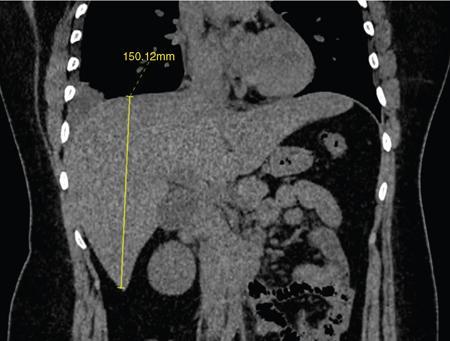

Ritu K. Kashikar, Shrinivas B. Desai Knowledge regarding normal dimensions of organs is important as visceromegaly is the first and often only abnormality in a variety of disorders. The radiologist should also be aware of normal diameters of vessels and ducts because an increase in size is usually a pointer to pathology in the organ. This chapter is a lucid review of normal sizes of organs, vessels, duct and also focuses on which section and location should size be measured to avoid interobserver variation. The liver is the largest organ in the abdomen. Hepatomegaly is a common condition and often the first clinical and imaging feature of various disorders. It is hence imperative for the radiologist to know the normal size and the section on which measurements should be taken. USG is commonly used to measure liver size. The longitudinal view is commonly used to measure liver size. The liver is considered normal in size if on longitudinal scan through the midhepatic line the liver measures 13 cm or less. This is true in approximately 93% individuals Measurement more than 15.5 cm suggests hepatomegaly in 75% cases (Figs. 9.3.1 and 9.3.2) (Table 9.3.1). Hepatomegaly is also suggested by an inferior angle of more than 45 degrees in the left lobe and more than 90 degrees in the right lobe. The normal liver measures approximately 6.5 cm first 3 months of age and reaches a size of 12.5 cm by 10–12 years of age. Liver size can be measured on unenhanced or enhanced CT. On CT the liver measures 10–12.5 cm in the midclavicular line on an average. A liver measuring more than 15.5–16 cm in the midclavicular line is considered enlarged. The midclavicular line measurement is done in coronal plane (Fig. 9.3.3). Another important measurement is the size of caudate lobe. The caudate to right lobe ratio (C/RL) is a measurement used to diagnose caudate lobe hypertrophy and right lobe atrophy which is important in the diagnosis of cirrhosis. The axial section immediately below main portal vein bifurcation is used for measurements. The following lines are drawn on the liver (Fig. 9.3.4). C/RL: In an adult patient of average weight (60 kg), the estimated liver volumes can range from 1024–1302 cm3 (Fig. 9.3.6). USG and Doppler provide important information regarding patency of artery in postoperative/transplant setting. Normal hepatic artery waveform is pulsatile and of low resistance. The normal resistive index measures 0.7. High or low resistivity index (RI) indicated pathology. The measurements of the hepatic arteries bare importance in transplant imaging. The diameter and length of the arteries are best measured on CT angiogram images. Arteries smaller in calibre than 2 mm may be difficult to anatomize. Replaced RHA is often longer in length than standard arteries. The normal diameters of the hepatic arteries are mentioned in Table 9.3.2 (Figs. 9.3.7–9.3.9). The portal venous system is valveless and hence its diameter is influenced by respiratory variations. The portal venous diameter is greatest during inspiration and hence all measurement should be made in this phase (Table 9.3.3). The diameter of portal vein has importance in diagnosing portal hypertension and USG is often used for this purpose. USG also provides other important parameters like flow velocity and volume flow which are relevant in the setting of portal hypertension. The normal portal venous velocity measures 15–18 cm/sec.(Fig. 9.3.10)

Midclavicular line

Measurement of liver size on CT